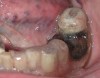

An alginate impression was taken bedside. The impression was poured in dental stone, and the cast was trimmed in the hospital dental laboratory. A 0.060-inch vacuum formed splint was fabricated (Figure 1). Cellulose dressing (Surgicel®, ETHICON, Inc., www.ethicon.com) was folded into a square and placed directly on the socket. The vacuum-formed splint was placed over the extraction site to apply pressure and to secure desired position (Figure 2). Hemostasis was achieved, and the splint was kept in place for 2 days. On removal, bleeding ceased, and the patient was subsequently discharged.

Figure 1  Fabrication of a 0.060-inch vacuum-formed splint.

Figure 1

Figure 2  Placement of the vacuum-formed splint over the extraction site.

Figure 2